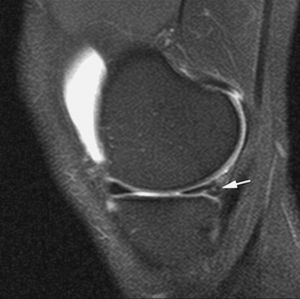

El síndrome de choque anterior es una causa relativamente frecuente de dolor crónico de tobillo, especialmente en deportistas sometidos a estrés repetido del tobillo en dorsiflexión («tobillo de futbolista»). Este proceso produce la existencia de prominencias óseas en el margen anterior del techo tibial, generalmente asociadas a otras en el área correspondiente sobre el margen opuesto del astrágalo. Estos osteofitos pueden chocar entre sí, especialmente con la dorsiflexión del tobillo, y atrapar tejidos de partes blandas. La RMA es de gran utilidad en la valoración de la afectación condral y la sinovitis (fig. 11) en el receso capsular anterior del tobillo19,23.

Fig. 11.--Síndrome de choque anterior. Corte sagital de RMA potenciado en T1 en el que se observan espolones óseos en el reborde tibial anterior y en la vertiente dorsal del cuello del astrágalo (flechas).